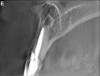

Figure 3a  The 3D capability of the CBCT shows the full extent of the horizontal fracture, as well as the fracture of the buccal and palatal plates.20

Figure 3a

Figure 3b  The 3D capability of the CBCT shows the full extent of the horizontal fracture, as well as the fracture of the buccal and palatal plates.20

Figure 3b

Figure 3c  The 3D capability of the CBCT shows the full extent of the horizontal fracture, as well as the fracture of the buccal and palatal plates.20

Figure 3c

Figure 3d  The 3D capability of the CBCT shows the full extent of the horizontal fracture, as well as the fracture of the buccal and palatal plates.20

Figure 3d

Initially, case studies appeared in the endodontic literature in which patients underwent CBCT imaging for the purposes of diagnosis20-22 and presurgical treatment planning.19 Recent reports have successfully shown the use of CBCT to locate missed canals,23 detect the extent of dentoalveolar fractures,20 identify resorption patterns,22 and compare cystic with granulomatous periapical lesions.17 Figure 2A through Figure 2C show a case in which the missed canal was suggested by periapical radiographs but confirmed with CBCT.24 Similarly in Figure 3A through Figure 3D, the additional diagnostic information attained from CBCT confirmed the diagnosis and extent of the root fracture, which initially was observed in the periapical radiographs (Figure 4A and Figure 4B).20 Notably, the extent of the lingual fracture as well as any alveolar complications could be visualized by CBCT only.